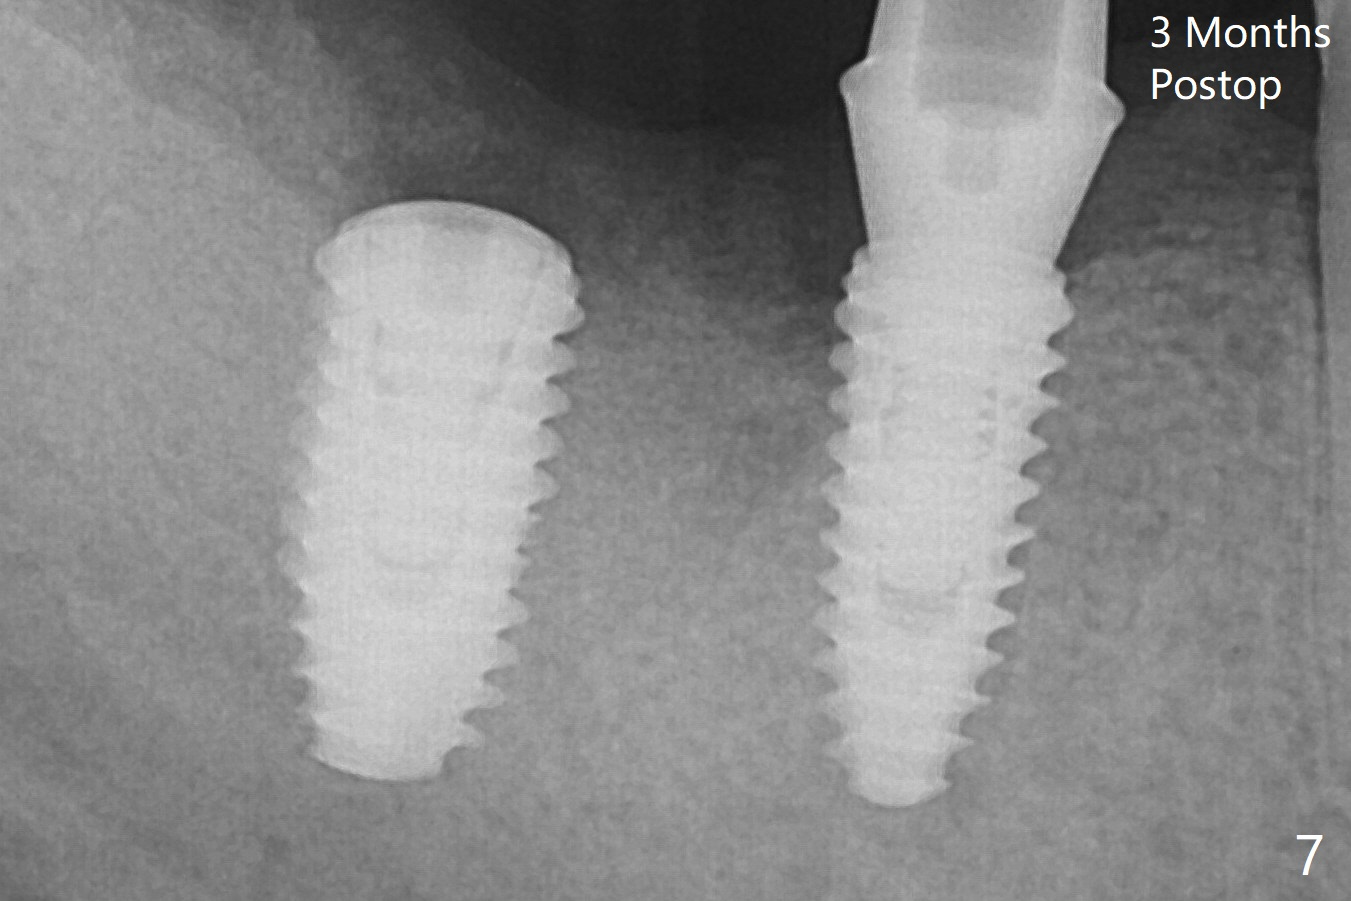

The loose implant is pushed distal (Fig.4 arrow) with placement of autogenous bone mesial (*). The stable implant at #30 (Fig.3) and its abutment (Fig.4) are used as a post to hold periodontal dressing, which covers the wound at #31 after placement of collagen plug and suturing. The bone graft seems to remain in place, while the implants remain parallel to each other 3 months postop (Fig.7). The implant is uncovered with placement of a 6.8x7 mm healing abutment 4 months postop. When a cementation abutment (4.5x5.5(4) mm) is placed, the buccal margin is much lower than the lingual. The patient enjoys mastication with the new implant crowns 3.5 months post cementation; the bone density around the implant at #31 increases (Fig.9).